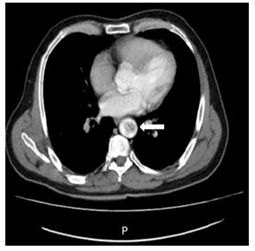

En búsqueda de fuente embólica se realiza un ecocardiograma transesofágico (ETE) (ver Figura 3 y 4 ), donde se evidenció placas ulceradas penetrantes en cayado aórtico distal y aorta descendente proximal de 9 mm con trombo móvil de 22 mm y 4 mm de espesor. A 4,5 cm de esta lesión en aorta descendente proximal, se aprecia una úlcera penetrante de 15 mm con gran trombo móvil de 35x9x11 mm.

Figura 4 Reconstrucción tridimensional ecocardiograma transesofágico: la flecha indica el trombo en aorta.